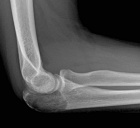

20 year old female who two months prior sustained a fall on to her right outstretched upper extremity and sustained an olecranon fracture for which she has undergone nonoperative management. She recalls that she had been experiencing discomfort in the right elbow prior to sustaining her injury.